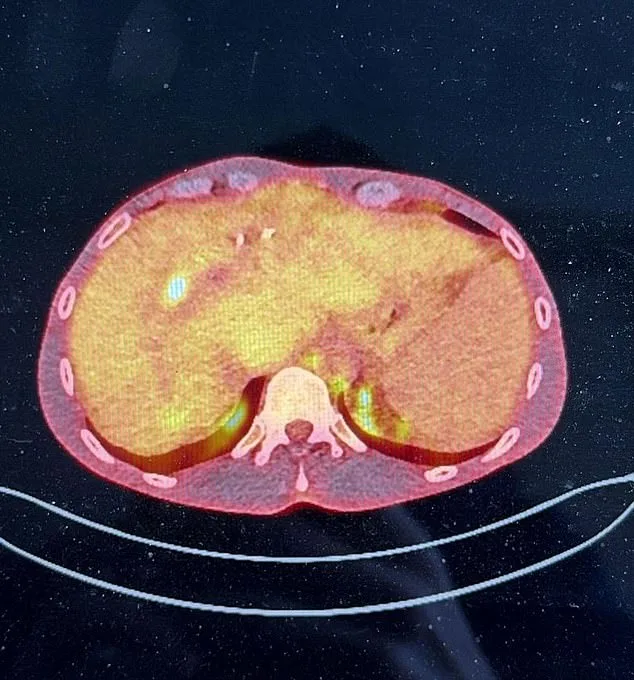

4mm Tumor Discrepancy Leaves Man with Rare Liver Disease Without Lifesaving Transplant

James Conradi, a 38-year-old father of one, is facing an agonizing dilemma: survival depends on a liver transplant, but the NHS has ruled him ineligible due to a tumor size discrepancy of just 4mm. The decision has left the family grappling with the possibility of losing him to a disease that could have been managed with timely intervention. His condition, primary sclerosing cholangitis (PSC), a chronic autoimmune disease that scars and blocks bile ducts, has progressed to an aggressive form of liver cancer called cholangiocarcinoma. This complication, which affects 6-15% of PSC patients, has left him with no viable options under current NHS criteria.

Conradi's wife, Laura Kay, a padel influencer, revealed the heartbreaking reality: 'The NHS won't perform the transplant because the tumours exceed 2cm. James's tumour is just 4mm over, but that's the difference between life and death.' The couple's son, Harrison, aged nine, is the emotional anchor of their family, a reminder of the future they are fighting to preserve. Without a transplant, Conradi's prognosis is dire. His liver, already damaged by PSC, is now failing rapidly, and conventional cancer treatments are off-limits due to the extent of organ damage.